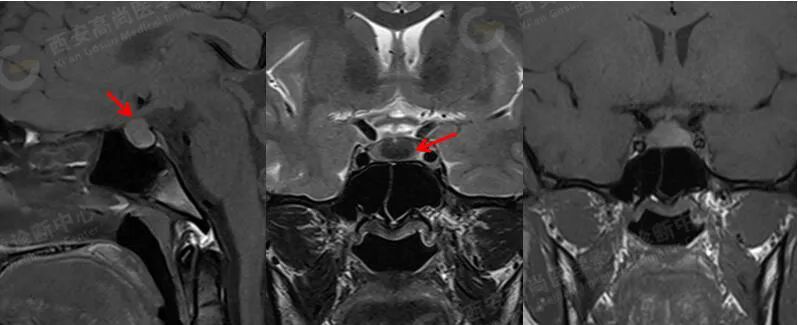

MRI 平扫+增强:垂体前后叶之间见大小约 1.6 cmX1.4 cmX1.3 cm 的囊状短 T1 长 T2 信号,边缘清晰,视交叉受压,垂体柄受压显示不清,垂体前叶变薄,垂体前后叶之间囊状病灶未见明显强化,边缘清晰。

诊断:垂体前后叶之间囊状病灶,考虑 Rathke 囊肿。